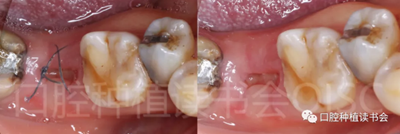

5.3.8 術(shù)后第3周,拔除48近中傾斜阻生智齒,觀察47位點(diǎn)愈合良好(圖21)。

圖21 拔除傾斜阻生的48,利于47后期的修復(fù)。

5.3.9 術(shù)后第6周,47行種植2期手術(shù),可見種植體周圍愈合良好,牙齦成型后,旋入愈合基臺(tái)(圖22)。

圖22 種植體周圍獲得了良好的骨整合。